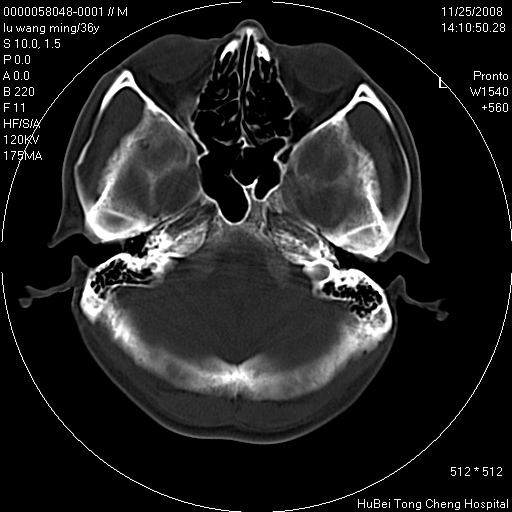

患者 男,36岁。头部烧伤36年伴溃烂,经久不愈。患者几个月大时,倒入火炉不幸烧伤头部,后长期溃烂,经久不愈。

临床诊断:1)头皮烧伤并感染。2)颅骨病损?

颅脑ct轴位平扫(层厚、层距均匀10mm),图像如下:

以骨质破坏为为,边缘呈虫噬样改变,多砂粒样钙钙化或死骨,伴软组织及硬膜外积脓,考虑为结核感染可能性大,建议细菌培养。

额顶局部骨质破坏缺损

患者有明确的病史,且经久不愈,更该考虑软组织化脓性感染,颅骨损害伴硬膜下下积脓

结合病史考虑颅骨慢性骨髓炎

结合病史考虑颅骨慢性骨髓炎伴硬膜外积脓。

结合病史考虑颅骨慢性骨髓炎;但局部见一软组织肿块,用炎症不好解释,应增强除外肿瘤。

骨质破坏,边缘呈虫噬样改变,结合患者明确烧伤史,经久不愈,考虑软组织化脓性感染,颅骨损害伴硬膜下积脓。

结合病史考虑颅骨慢性骨髓炎伴硬膜外积脓,软组织溃烂恶变不排除,建议活检。